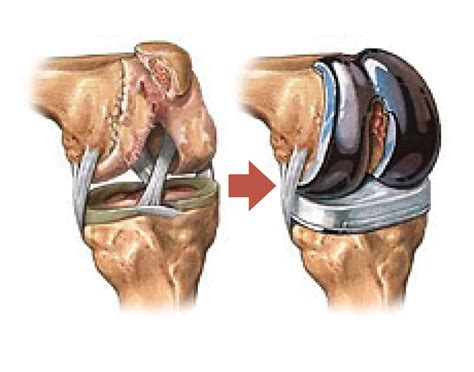

Cuanto Dura Una Protesis De Rodilla, ¿Cuánto tiempo dura una prótesis de rodilla Todo lo que debes saber, 6.64 MB, 04:50, 119,988, Top Doctors LATAM, 2017-08-23T17:42:43.000000Z, 3, SALUTARIS MEDICAL CENTER: Prótesis total de rodilla, salutarismedicalcenter.blogspot.com, 1600 x 721, jpeg, WebLa mayoría de las articulaciones de la rodilla artificiales dura de 10 a 15 años. Algunas duran hasta 20 años antes de aflojarse y necesitar que las reemplacen de nuevo. Las. WebEl tiempo medio habitual de una baja laboral por prótesis de rodilla es de 6 a 12 semanas. Pacientes con trabajos menos demandantes pueden volver a trabajar tan pronto hagan. WebNormalmente, se pueden retomar las actividades cotidianas a las 3 o 6 semanas tras la cirugía. El programa de ejercicio físico de la recuperación en casa., 20, cuanto-dura-una-protesis-de-rodilla, Novedades y Muebles WebLa mayoría de las articulaciones de la rodilla artificiales dura de 10 a 15 años. Algunas duran hasta 20 años antes de aflojarse y necesitar que las reemplacen de nuevo. Las. WebEl tiempo medio habitual de una baja laboral por prótesis de rodilla es de 6 a 12 semanas. Pacientes con trabajos menos demandantes pueden volver a trabajar tan pronto hagan. WebNormalmente, se pueden retomar las actividades cotidianas a las 3 o 6 semanas tras la cirugía. El programa de ejercicio físico de la recuperación en casa.

WebPodemos concluir diciendo que, en líneas generales, la supervivencia de las prótesis de rodilla es de unos 15 años de media. Esto puede variar mucho en cada uno. WebEl tiempo de hospitalización después de la implantación de la prótesis de rodilla es de 3 a 5 días, aunque se exigirá al paciente que empiece a moverse prácticamente desde el.

WebLa supervivencia (o cuánto duran las prótesis de rodilla), según el especialista, Doctor Villanueva, incluso en pacientes jóvenes, pueden sobrevivir de 15 a 20 años, en el 90. WebEl tiempo que puede llevar colocar una prótesis de rodillas es de 60 a 90 minutos. Con el nuevo material de reemplazo de la rodilla, los componentes se. Web¿Cuánto dura una Prótesis de rodilla? Al igual que otros tipos de endoprótesis, una prótesis de rodilla tiene una vida útil limitada. Con una cirugía adecuada y sin complicaciones. WebUna cirugía de prótesis de rodilla no dura ni mucho ni poco, si no lo justo y necesario. La recuperación tras una operación de prótesis de rodilla puede ir de 4 a 6. WebEl 2 de octubre me sometieron a una protesis de rodilla als 12 dias juntlo mucho liquido me volvieron a meter al quirofano para hacer una limpieza por q teni. WebA los 50-60 los pacientes quieren vivir las actividades y el tipo de vida correspondiente a su edad y así sucesivamente. En general las prótesis de rodilla no tienen una duración.